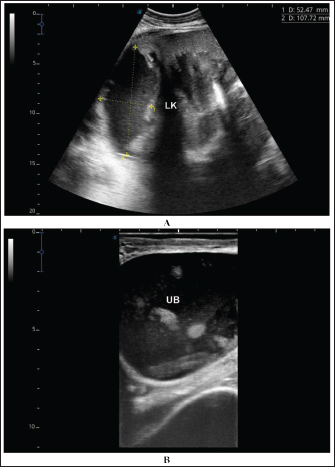

Fig. 9. Ultrasonographic findings in the camels with abscessation of the left kidney (LK). Image A shows a large abscess in camel number 15 with isoechoic contents and a thick capsule. Image B shows a small abscess in the left kidney of camel number 16 with heterogeneous contents.

Fig. 10. Ultrasonographic findings in camel number 17 with abscessation of the left kidney. Image A shows a large abscess compressing the parenchyma of the left kidney (LK) with isoechoic contents. Image B shows the urinary bladder (UB) in the same animal with echogenic deposits that appeared highly echogenic compared with the echogenic urine.

Ultrasonographic findings in camel number 9 with right kidney abscesses are shown in Figure 7, where the lesion appeared compressing the parenchyma of the right kidney. Its contents are hyperechoic, and its capsule is thick. Figure 8 shows sonographic findings in camel number 11 with abscessation of the right and left kidneys. Abscesses measured 7.6 × 6.9 cm and 9.3 × 8.1 cm with isoechoic contents. A third abscess in the same camel was found within the left kidney. It was relatively large and was isoechoic. Ultrasonographic findings in camels 15 and 16 with abscesses of the left kidney are shown in Figure 9. A large abscess was found in camel number 15 with isoechoic contents and a thick capsule, while a small abscess was imaged in the left kidney of animal number 16 with heterogeneous contents. Figure 10 shows the ultrasonographic findings in camel number 17 with abscessation of the left kidney. A large abscess was found compressing the parenchyma of the left kidney with isoechoic contents. The urinary bladder in the same camel contained echogenic deposits that appeared to be highly echogenic.